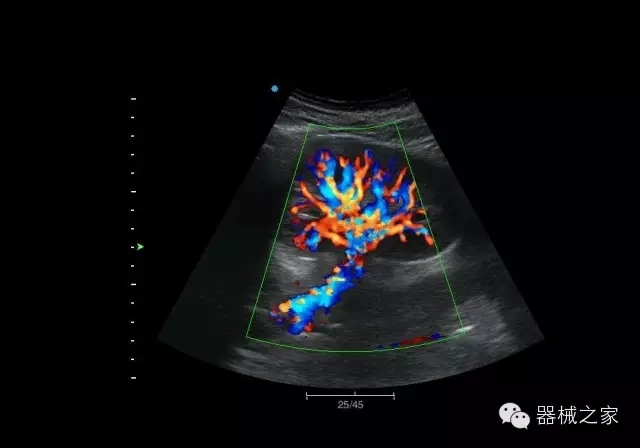

經(jīng)典產(chǎn)品:Apogee 1000

臨床圖片賞析

結(jié)甲

腎臟血流

肝血管瘤

產(chǎn)品特點(diǎn)

·屏幕可左右90度旋轉(zhuǎn);

·雙模操控;

·兩用提手;

·雙鋰電池;

·超輕機(jī)身;

·15寸高亮高清醫(yī)學(xué)顯示器;

·衛(wèi)星布局操控面板;

·一體化剪切板;

·多功能導(dǎo)航鍵;

“宏云”平臺

·采用移植自高端臺式彩超的“宏云”平臺技術(shù),使系統(tǒng)具有更優(yōu)秀的圖像效果;

人性化的設(shè)計(jì)

·內(nèi)置電池,輕巧的外觀設(shè)計(jì)以及臨床功能、軟硬件設(shè)計(jì)的人性化設(shè)計(jì),使系統(tǒng)在臨床多科室移動診查中,均從容應(yīng)對;

Fusion THI二代融合諧波成像

·在不同諧波頻率段獲得的信息進(jìn)行實(shí)時(shí)融合,既能獲得諧波圖像分辨率又能提高圖像的穿透力,降低圖像噪音;

XBeam多域復(fù)合成像

·通過頻域和空域角度進(jìn)行復(fù)合的圖像處理,能有效消除由于圖像離散化和圖像衰減引起的空間分辨率下降的不利影響,彌補(bǔ)原有圖像空間分辨率的不足,獲得更加清晰的圖像;

CFDA注冊證編號

·粵食藥監(jiān)械(準(zhǔn))字2014第2231316號